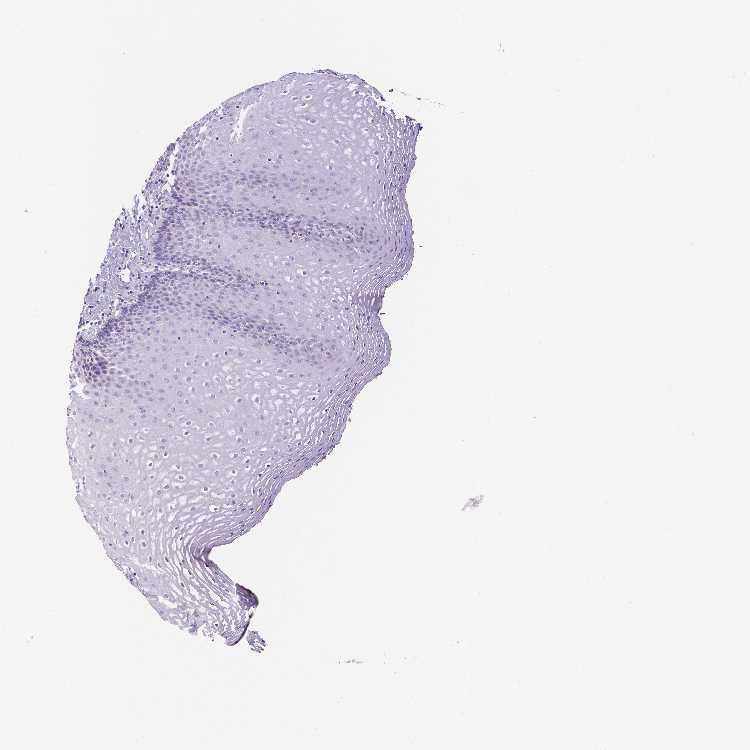

ESOPHAGUS - HPA RNA-seqi

The RNA-seq details section shows detailed information about the individual samples used for the transcript profiling and results of the RNA-seq analysis.

Information about each individual sample is listed below, including gender, age, a tissue section image and estimated fractions of cell types. nTPM (normalized transcripts per million) values give a quantification of the gene abundance which is comparable between different genes and samples.

Average nTPMi

Max subtype nTPM is the value for the subtype with the largest average nTPM across the subtype samples.

0.5

overview

Female, age 70

Esophagus sample 130

nTPM: 0.4

Cell types%

Squamous epithelial cells:

35

Smooth muscle cells:

15

Skeletal muscle cells:

5

Other cell types:

45

Male, age 38

Esophagus sample 131

nTPM: 0.8

60

20

Male, age 76

Esophagus sample 132

nTPM: 0.5

40